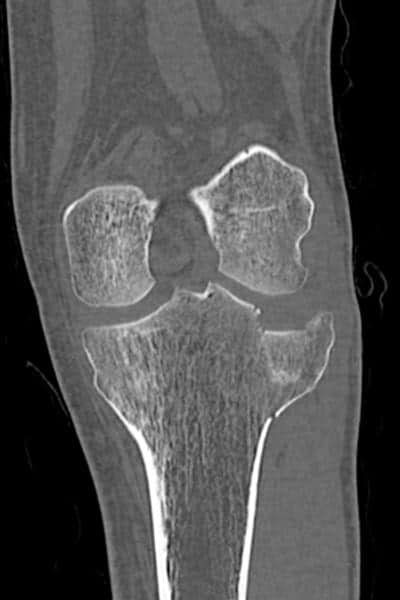

Tomodensitométrie – Scanner

Cet examen peut fournir au médecin des informations précieuses sur la gravité de la fracture et l’aiguiller pour le choix du traitement le plus adapté.

Scanner d’une fracture enfoncement du plateau tibial